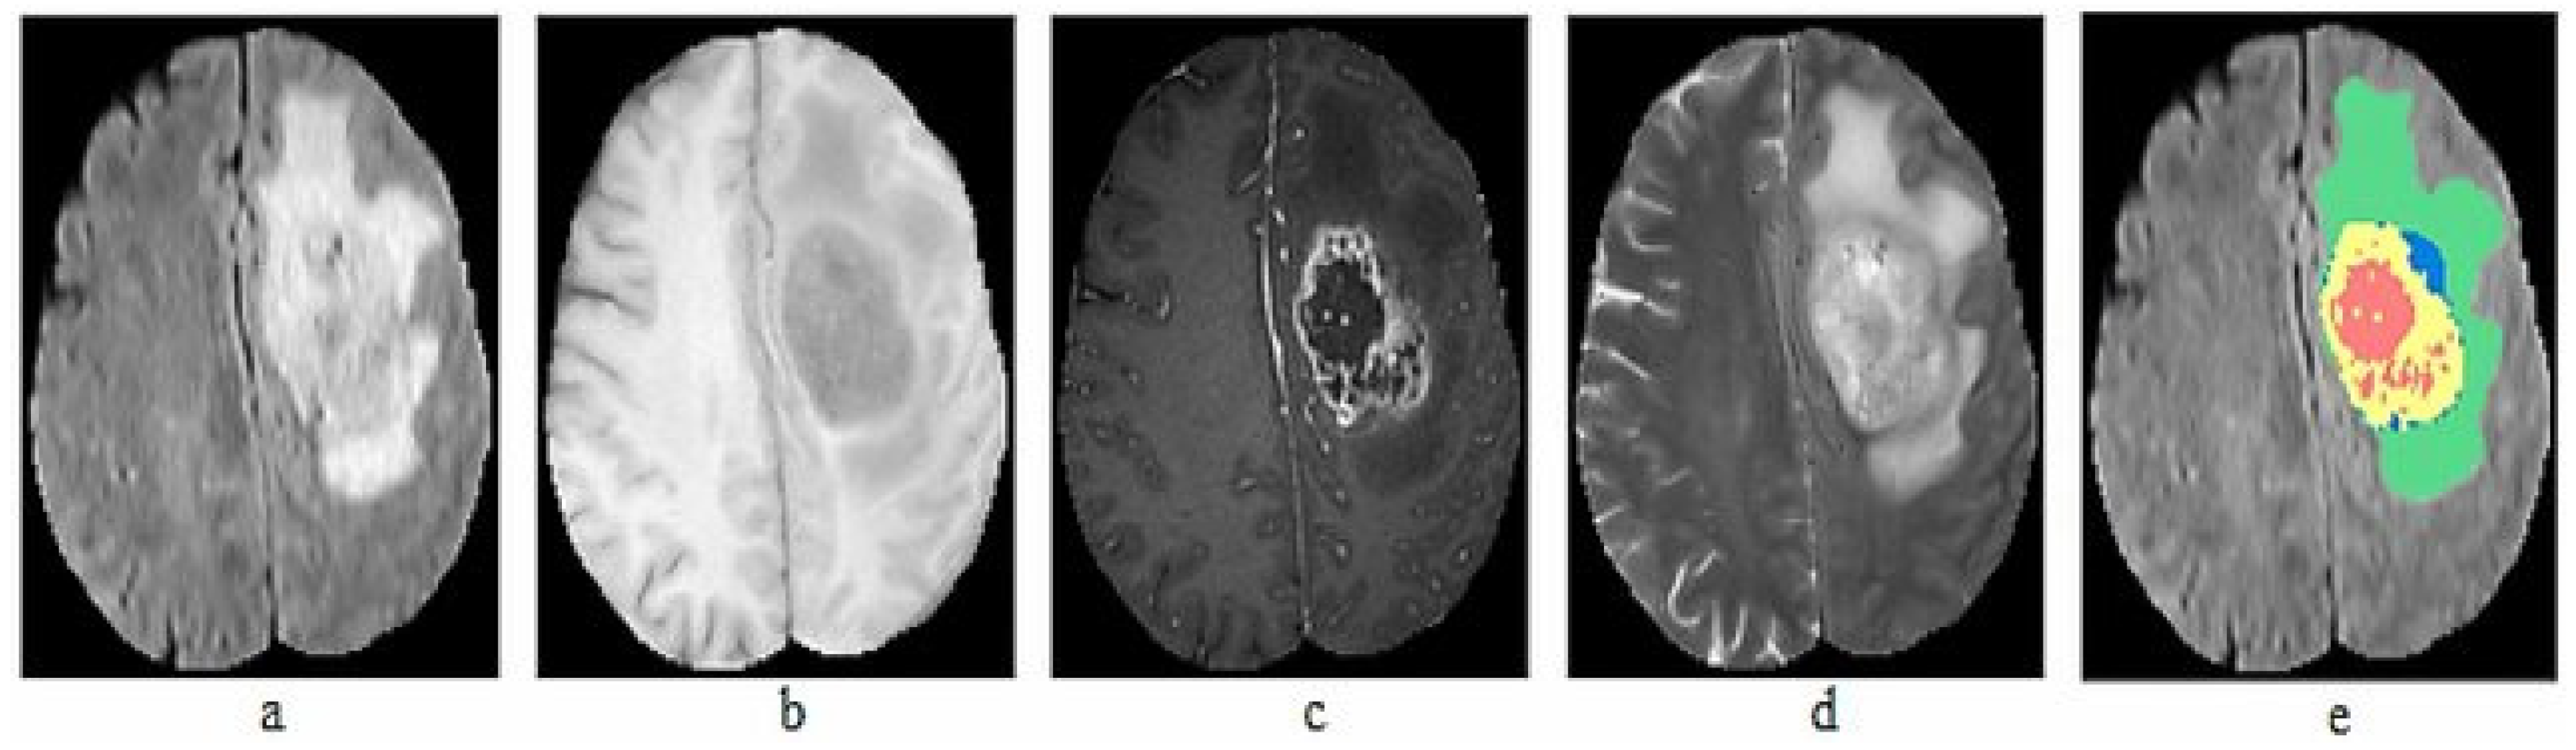

The BraTS dataset is compiled from MRI scans of patients with brain tumors, contributed by multiple medical centers worldwide. The dataset includes anonymized scans and corresponding manual segmentations prepared by experienced radiologists. In total, we used seven datasets from 2012 to 2018, with a total of 564 images. The collected datasets include 5106 images of both HGG and LGG. Each patient in the dataset is represented by four MRI images and ground truth: T1, T1-c, T2, FLAIR volumes and Ground truth, as illustrated in Figure 2.

Figure 2.

Sample MRI Images of BraTS dataset (a) T1, (b) T1-c, (c) T2, (d) FLAIR, (e) Ground truth.